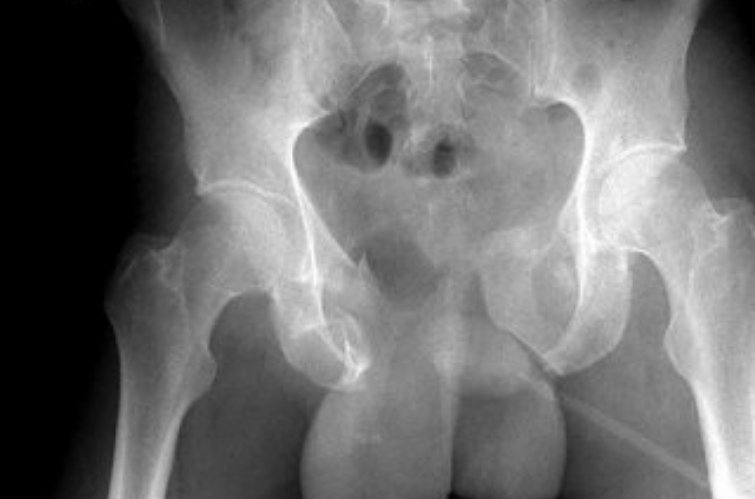

Mesmo em colisões de menor gravidade, o impacto da pelve contra o tanque pode causar hematomas, lesões genitais e traumas pélvicos. Um estudo publicado no Traffic Injury Prevention Journal mostra que 85% das fraturas pélvicas em acidentes de moto estão relacionadas ao contato direto com o tanque de combustível. Já pesquisas biomecânicas apontam que a postura do piloto e o formato do tanque influenciam diretamente a intensidade da pancada nessa região.

“O problema não é apenas o impacto em si, mas o que ele pode causar dentro do corpo. A bexiga cheia funciona como um balão pressurizado. Se ela rompe, o líquido contaminado se espalha e pode causar uma infecção gravíssima”, explica um trecho do relatório Pelvic Injury Potential and Motorcycle Gas Tanks, publicado por pesquisadores da SMARTER-USA.